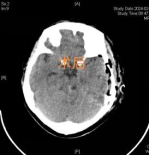

术中,病灶被切除时,电生理监测立刻显示陈女士右侧肢体感觉功能得到明显改善,且神经功能得到完整保留。术后在医护人员精心照料下,陈女士的右侧肢体肌力逐渐恢复。

术后复查:病灶完整切除

各项复查显示,病灶已被完整切除、颅神经功能均未受损。陈女士右侧肢体感觉和运动功能得到明显改善,她阴郁的脸上终于露出了久违的笑容。